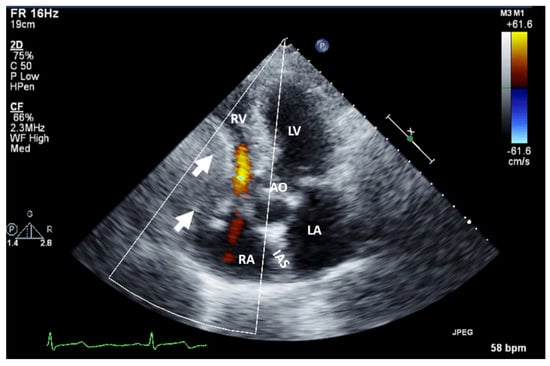

Figure 5.

Two-dimensional transesophageal echocardiography (short-axis view at the level of the great vessels) showing a mass (arrow) on the port-a-cath in a patient with neoplasia and chemotherapy. It was an incidental finding. The mass disappeared after initiating anticoagulation treatment. AO, aorta; IVS, interventricular septum; LA, left atrium; LV, left ventricle; RV, right ventricle.